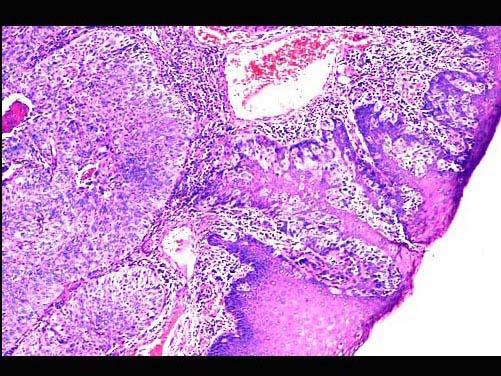

问题 患者男性,58岁,进行性声嘶2月,伴吞咽困难,临床检查示喉部新生物。活检镜下如图,正确的诊断是 ( )

选项 A.喉乳头状瘤 B.喉恶性淋巴瘤侵及固有腺体 C.喉低分化鳞状细胞癌侵及固有腺体 D.喉腺癌 E.喉高分化鳞状细胞癌侵及固有腺体

答案 C